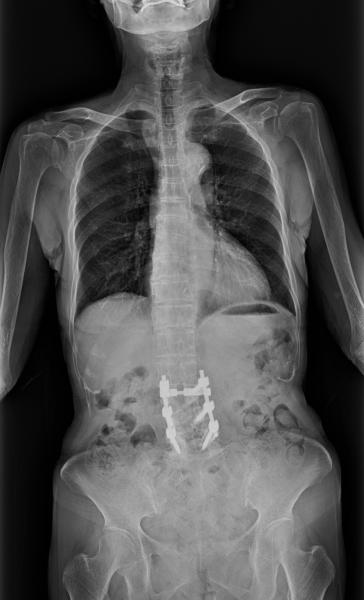

Nearby was Shimadzu Medical Systems, which broadened its appeal as a digital radiography (DR) neutral vendor by featuring Smart Stitch (from Canon), a long-imaging capability for spines and legs, and Dynamic Digital Radiography (DDR), a recently FDA-cleared capability that visualizes movement using conventional X-ray. Shimadzu collaborated with Konica Minolta in the development of DDR, combining Konica’s advanced image processing with its own RADspeed Pro X-ray imaging system. Shimadzu also framed its FDA-pending FLUOROspeed X1, a radiography/fluoroscopy (RF) table system, for supporting advanced RF features on a conventional table.

At AHRA 2019, Fujifilm Medical Systems USA sponsored a symposium on long-length DR. Gregg R. Cretella, the company’s national director of clinical operations, told ITN prior to the meeting that DR long-length detector technology and image processing algorithms are changing the utilization of this modality in spine imaging. On the exhibit floor Fujifilm showcased mammography developments designed to improve image quality and lower patient dose.